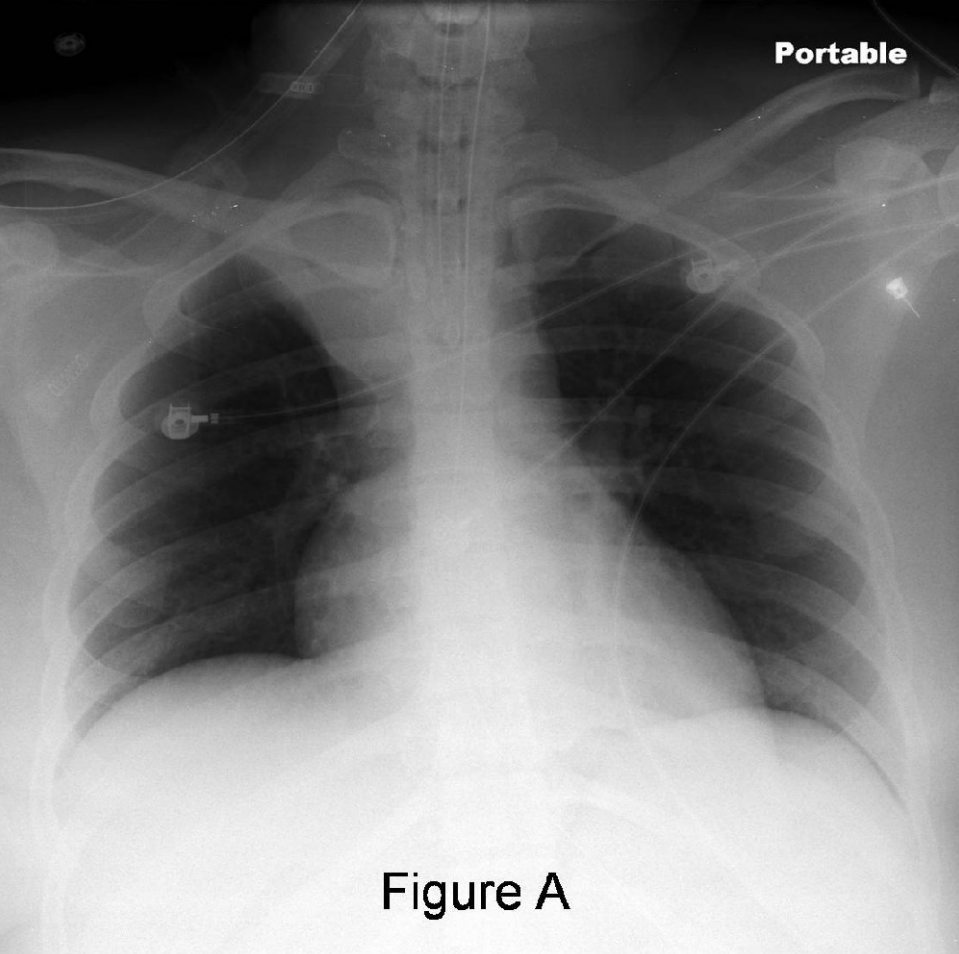

• Interstitial fluid:

• patchy whiteness on both sides

• enlarged heart